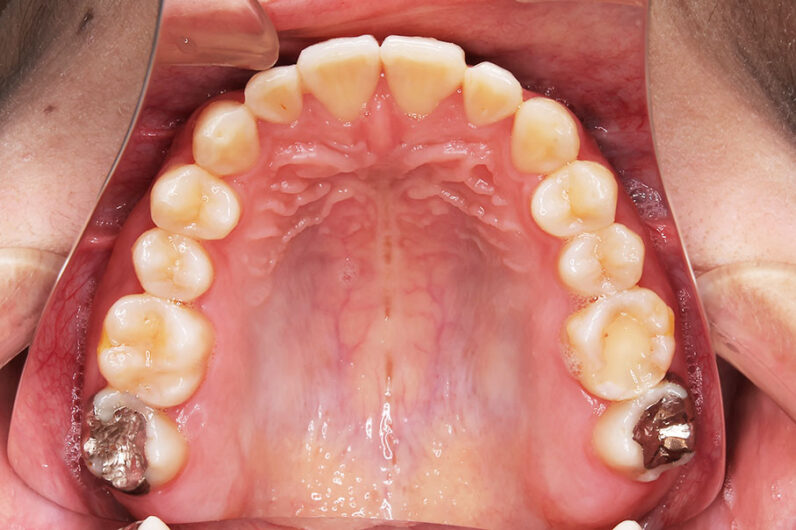

受け口を気にされ、他院からの紹介で来院された患者さんです。

小学2年生、生え変わりの時期から小児矯正を開始しました。

小児矯正で前歯の咬み合わせを改善し、

永久歯列完成後の中学生から非抜歯治療にて本格矯正を開始。

配列し仕上げました。